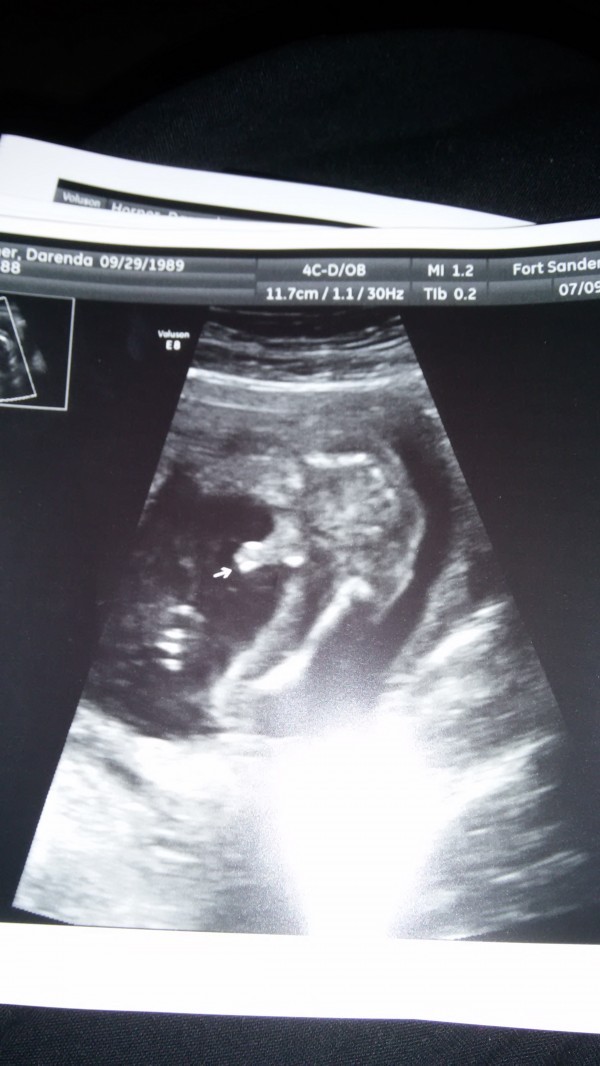

The first is his left foot. They are both turned in but that's the only picture they could get. The second needs no explanation lol